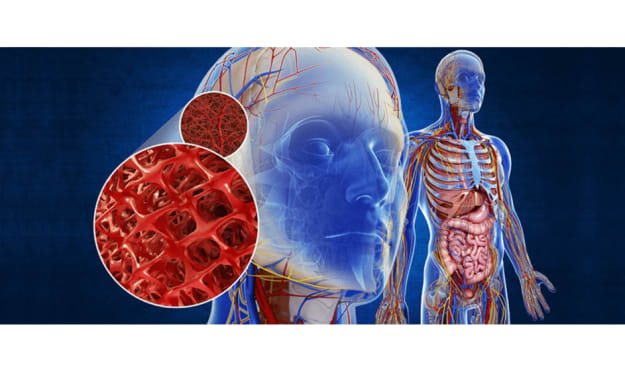

Is our nervous system this complex ???

Title: Unveiling the Power of Synapses: The Incredible Communicators of the Nervous System Introduction: What if I told you that something 1000 times thinner than a piece of paper, more numerous in you than grains of sand on a beach, holds the key to understanding the immense power of the smallest elements in your body? Welcome to the world of synapses, the meeting points between neurons that transform the structure of your nervous system into an extraordinary network of communication and intelligence.

Is our nervous system this complex ???

Title: Unveiling the Intricacies of Neuronal Communication: The Power of Action Potentials Introduction: Imagine a world where every thought, feeling, and action can be communicated by simply pressing a button. It would be like using a simplistic app that emits a constant and uniform ping, conveying everything from "I'm cold" to "I love churros" to "I need to breathe." Interestingly, this concept mirrors how neurons send electrical impulses responsible for all our actions, thoughts, and emotions. Neurons transmit signals through a remarkable phenomenon called action potentials. In this article, we will delve into the fascinating world of neuronal communication, exploring the mechanisms behind action potentials and their significance in our daily lives.

Is our nervous system this complex ???

Title: The Intricacies of the Nervous System: Understanding Its Functions and Organization Introduction Every morning, we go through various routine actions that seem mundane, such as waking up from a dream, getting dressed, having breakfast, and attending to our pets. However, these actions are not merely part of our morning rituals; they are all manifestations of the incredible capabilities of our nervous system. From processing dreams to sensing temperature changes and making decisions, our nervous system controls every aspect of our being. In this article, we delve into the fascinating world of the nervous system, exploring its anatomy, organization, communication, and the consequences of damage.